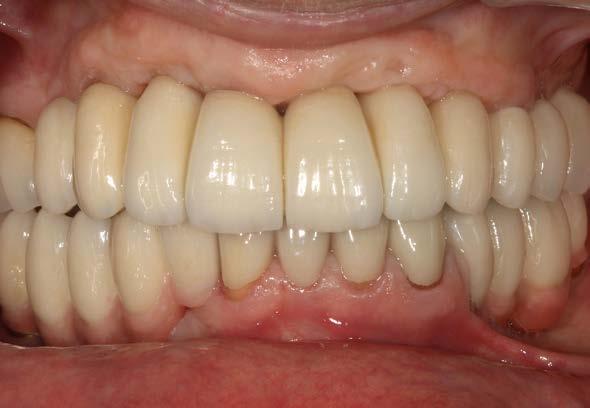

Figuras 2 y 3. Imágenes intraorales de la paciente, donde podemos observar la pérdida ósea acusada en algunos puntos con exposición de los componentes protésicos, así como transparencia incluso de las espiras de los implantes como el situado en posición 13 a través del tejido gingival.

Figura 7 y 8. Fotografías de la prótesis de carga inmediata. En ellas observamos ambas prótesis (superior e inferior) colocadas horas después de la cirugía.

Figuras 10 y 11. Caso finalizado 6 meses después, con las prótesis definitivas colocadas.